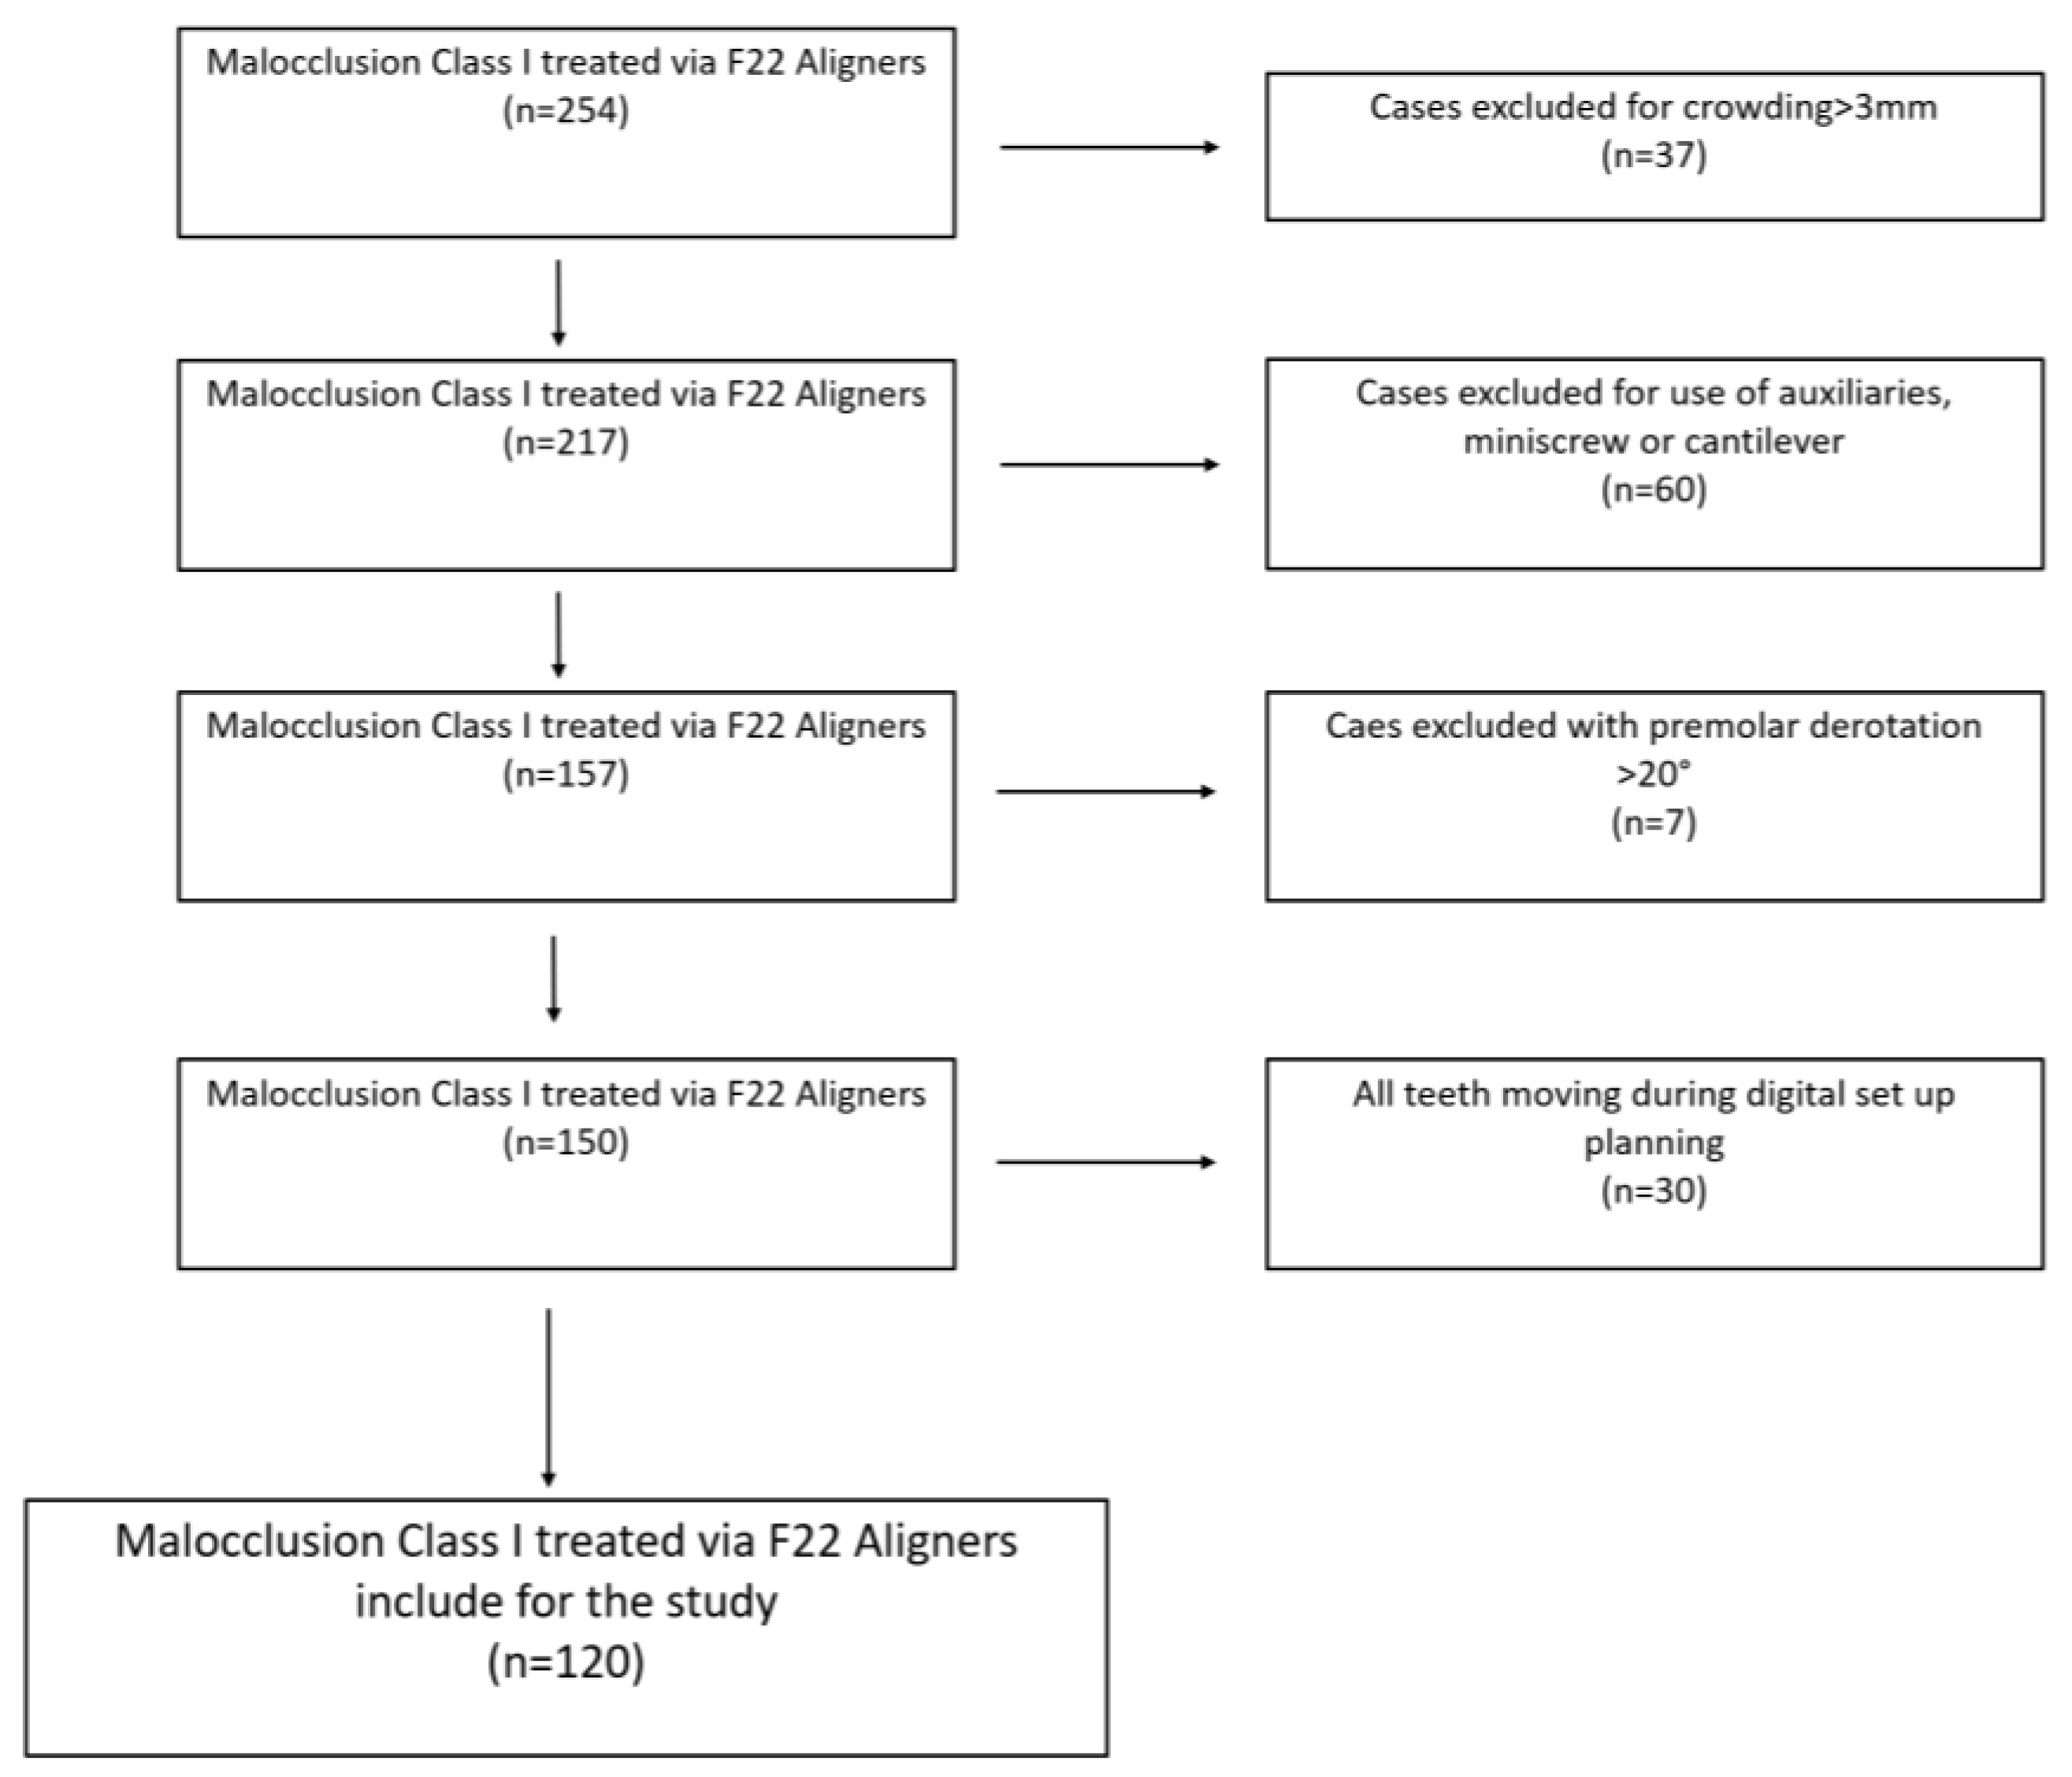

2.1. Sample Selection

- Class I dental malocclusion with minimal crowding (≤3 mm) in both arches [32], treated with a series of 12–20 aligners per arch.

- No use of auxiliaries (derotation elastomeric chains, inter-arch elastics or extrusion elastics), miniscrews, cantilevers or vestibular or lingual fixed partial appliances.

- Grip points and IPR (interproximal reduction) were permitted.

- Planned derotation of rounded teeth ≤ 20° (premolars and canines) is included.

- The use of grip points positioned for derotation ≥ 10° of rounded teeth and >20° for mandibular incisors and maxillary lateral incisors, which have a mesiodistally narrow clinical crown. The triangular grip points were applied with the long side in the direction of force application.

- No previous or active periodontal disease at the beginning of orthodontic therapy.

- Presence of at least one posterior tooth (first or second molar) per quadrant that had not been planned to move.

- F22 Aligners were worn for 2 weeks prior to passing to the following step.

- F22 Aligner therapy completed with adequate patient compliance (20–22 h per day), as documented in a personal diary.